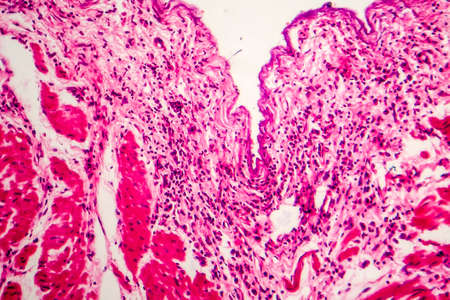

Condyloma acuminatum, also known as genital warts. Light micrograph, photo under microscope

Condyloma acuminatum, also known as genital warts. Light micrograph, photo under microscope